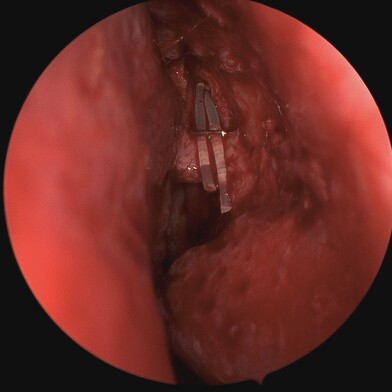

The endoscope is inserted through the nasal cavity to visualise and access the lacrimal sac and nasal bones. The bone is drilled away endoscopically, and a similar new pathway is created without external incisions. A mucosal flap is created to line the new passage connecting the lacrimal sac to the nasal cavity, ensuring proper drainage of tears. Silicone tubes or stents may be placed temporarily to keep the new pathway open and aid in healing.